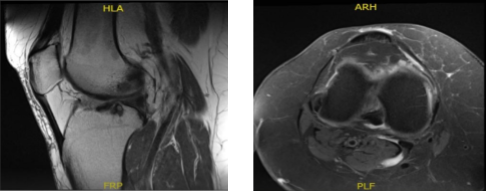

MRI-3T Right Knee Non-contrast

MRI results were presented and shown that there is a radial tear through the posterior horn of the medial meniscus. Tricompartmental cartilage loss, worst in the medial compartment where there is a focal full-thickness chondral defect. There is moderate partial-thickness patellar cartilage loss. Small joint effusion and Baker’s cyst.

MRI- Right Calf Non-contrast

The patient is here for a follow up with an MRI of the right calf to review. Results showed no evidence of tibial stress fracture or stress reaction. Calf musculature is normal.

Degenerative changes within the knee as well as a small popliteal cyst are better appreciated on the recent knee MRI. Limited evaluation of the ankle demonstrates chronic plantar fasciitis and a partial tear at the origin of the central cord.